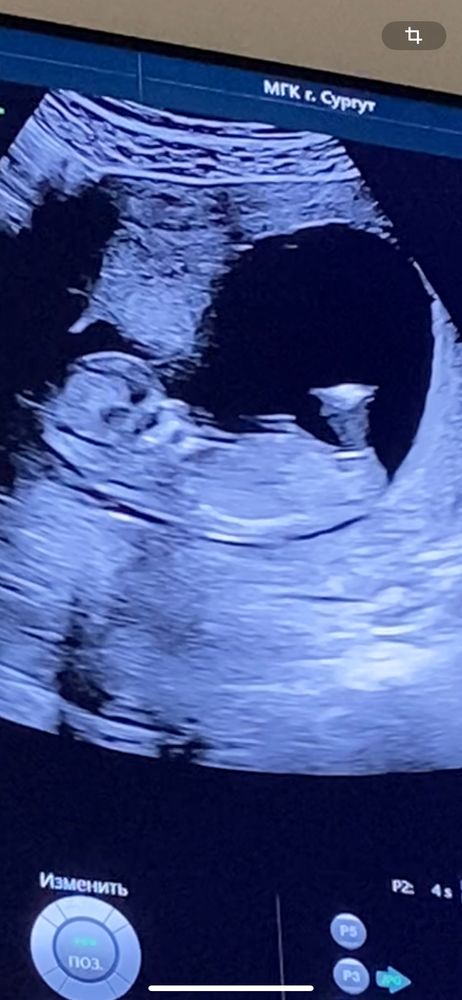

Здравствуйте! Кто нибудь может по половому бугорку определить пол ребенка? Распирает уж очень от любопытства. Я на 1 скрининге предположила пол ребенка и врач со мной согласилась, хотя до этого сказала что пол невозможно определить.